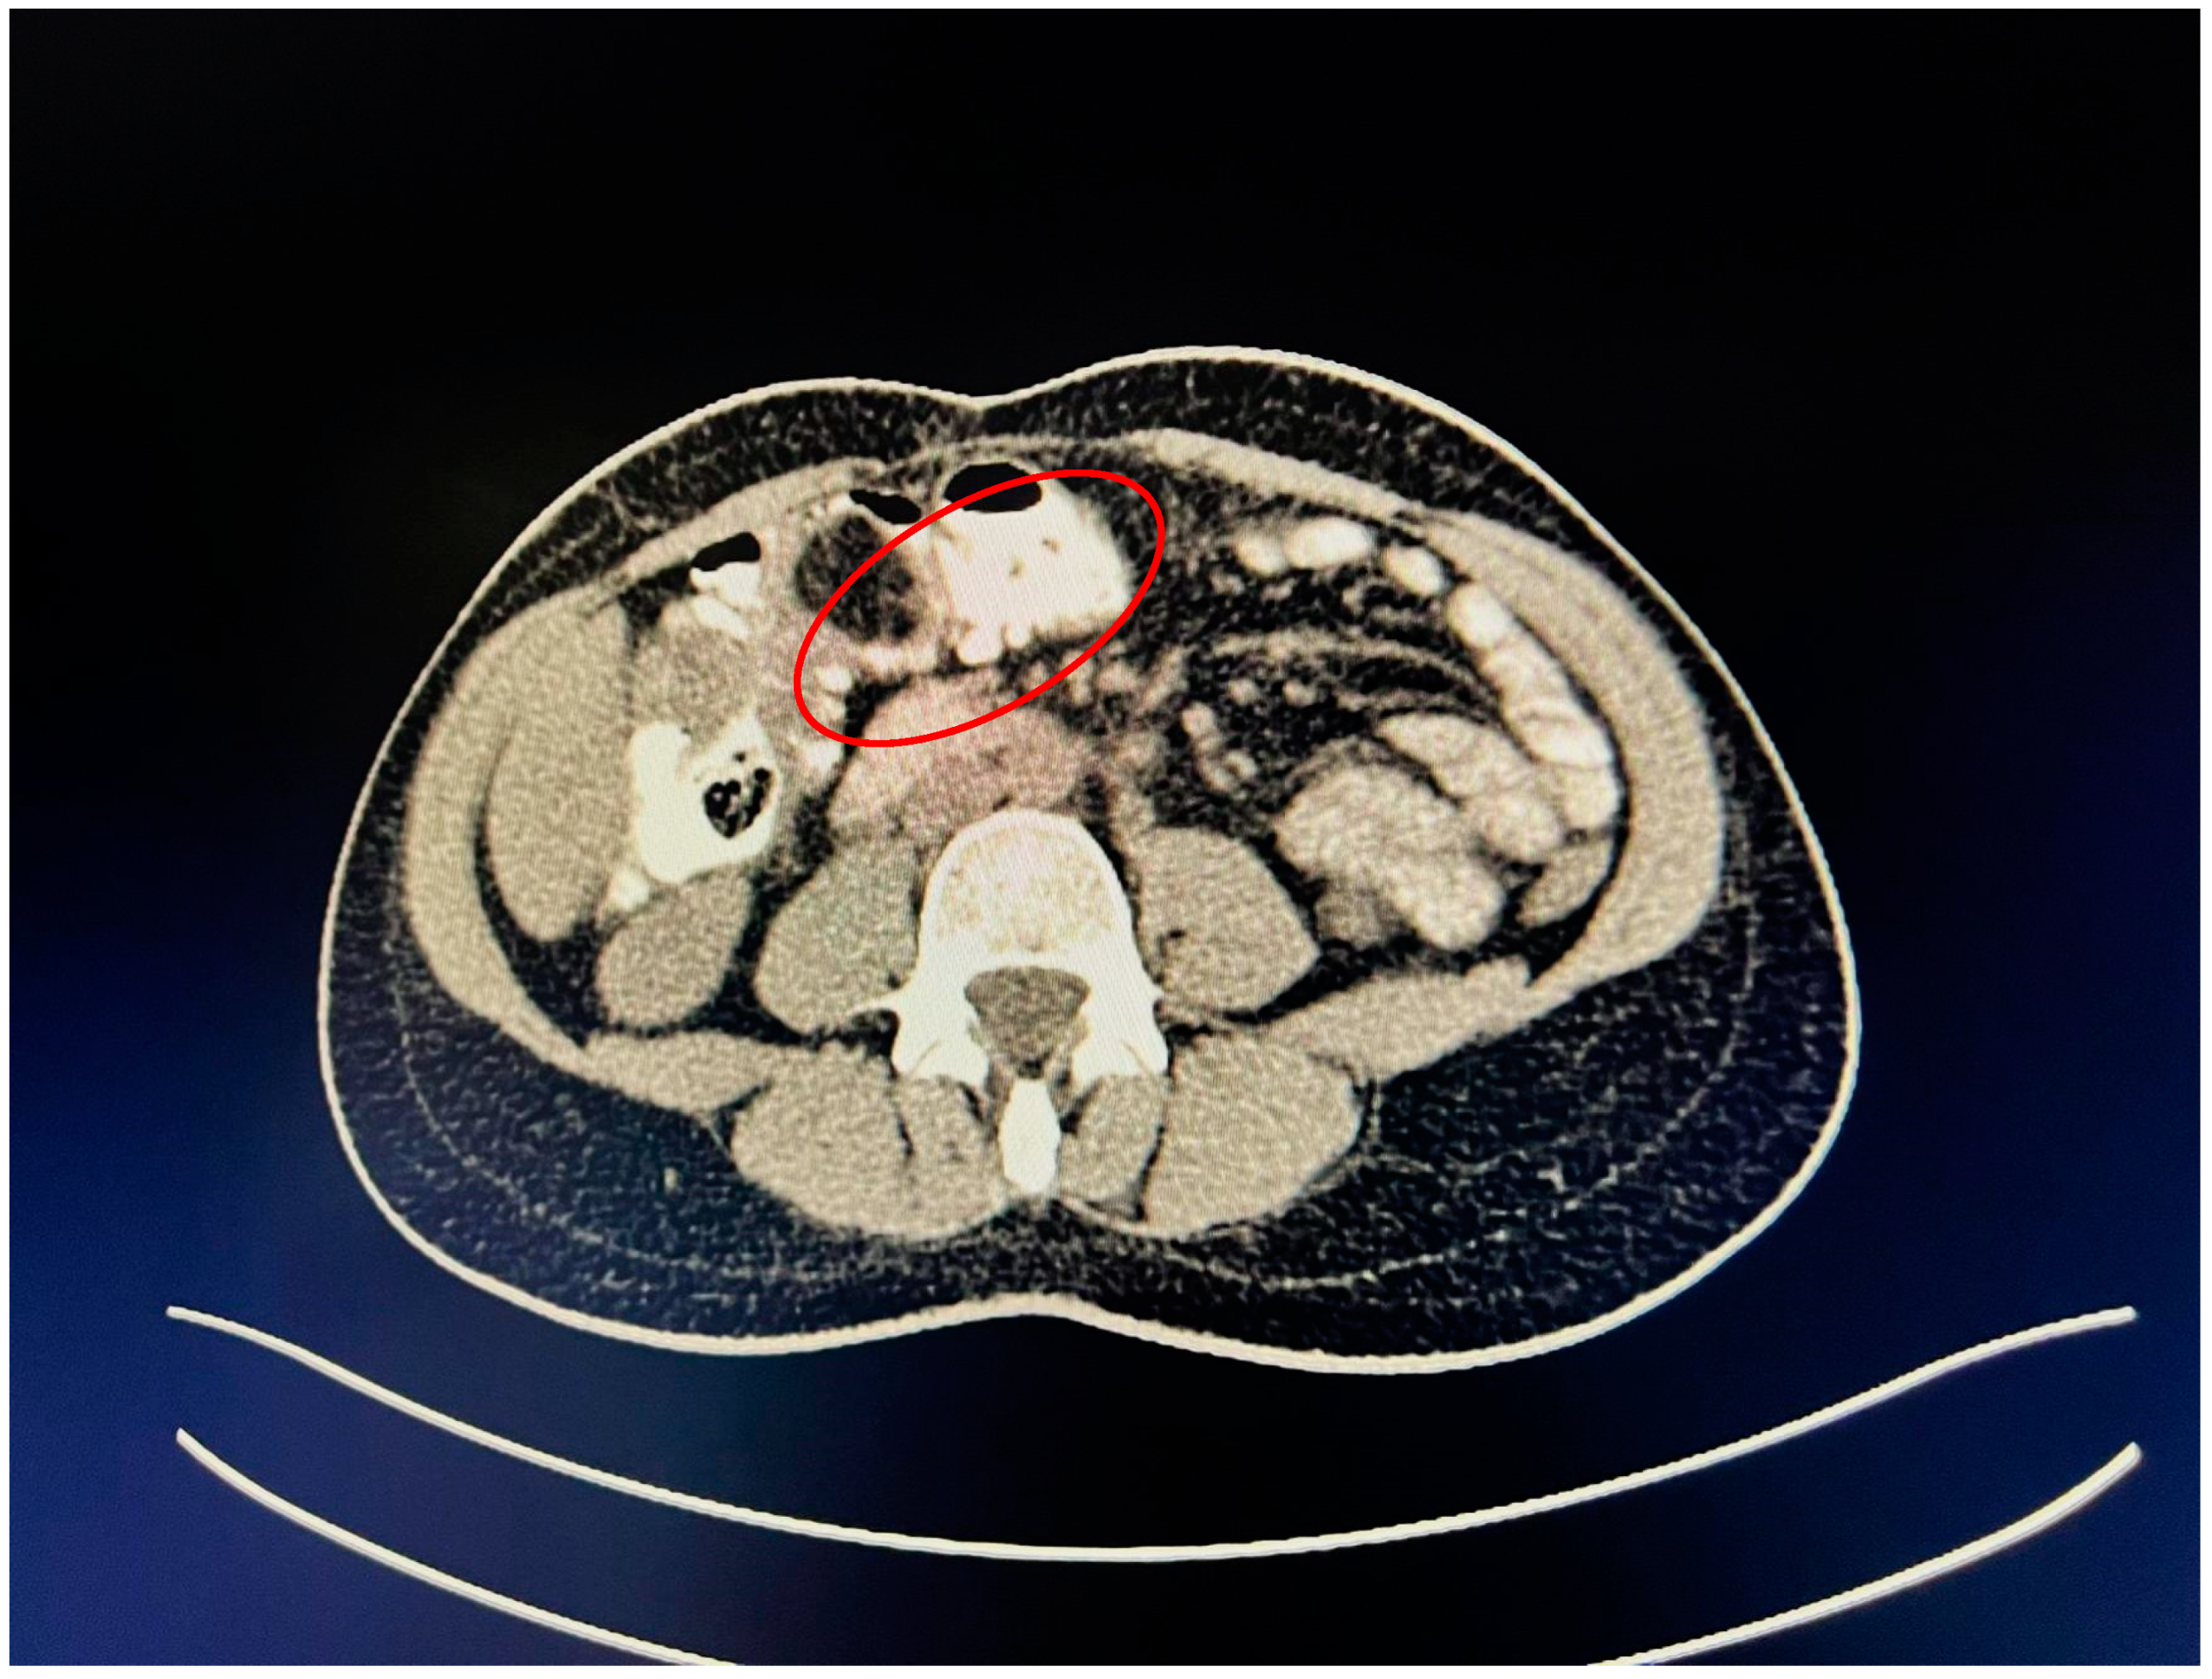

A contrast-enhanced computed tomography (CT) scan conducted on the day of admission revealed circumferential parietal thickening of a maximum of 21 mm at the hepatic flexure of the colon. This thickening extended over a length of approximately 45 mm, resulting in filiform, axial stenosis of the lumen, without any overlying distension of the colonic frame. The parietal thickening was moderately iodophilic and accompanied by discrete linear-type densification of locoregional fat, which was most likely a desmoplastic reaction. A tumor formation with a maximum axial diameter of approximately 29/28 mm, extending craniocaudal on a length of approximately 27 mm, was located at the distal end of the parietal ingrowth with an intraluminal site. This tumor formation had a polycyclic contour, thin septa within, and a discrete lodophilic peripheral appearance. It appeared to have a wide base of implantation at the level of the postero-inferior wall of the colon; mild hepatomegaly in the liver, with a homogeneous structure and a regular surface, and the absence of focal primary or secondary lesions; adenopathies in the hepatic hilum with a maximum diameter of 16/12.5 mm and in the celio-mezenteric territory with a maximum diameter of 24/19 mm; microadenopathies with the gastro-hepatic ligament; and an absence of subdiaphragmatic fluid (Figure 1, Figure 2 and Figure 3).

Figure 3.

Mass resulting in filiform axial narrowing of the lumen without associated distention of the colon.